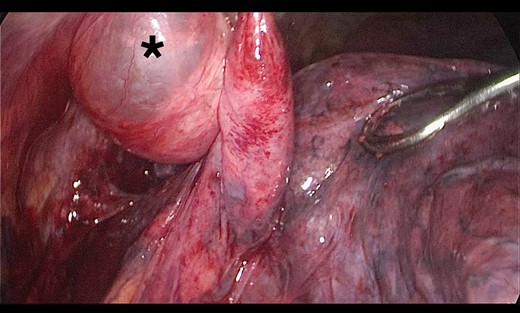

A 73-year-old male patient with a clinical history of COPD, lung emphysema and a 30-year smoking history was admitted to the ED due to a 24-h clinical picture of dyspnea immediately following a sudden bout of dry coughing. Physical examination showed a dyspneic patient, tachypnea of 25 rpm, heart rate of 85 bpm and blood Pressure of 135/75 mmHg along with central cyanosis. Chest exam showed a hyper-resonant right hemithorax along with reduced breath sounds. Initial chest X-ray revealed a large right-sided pneumothorax (Fig. 1). A right chest tube was placed in the ED. Emergency echocardiogram had no significant findings and spirometry showed suspected patterns of obstruction. Following patient stabilization, a high-resolution chest computed tomography (HRCT) was performed revealing extensive pan lobar emphysema throughout both lungs, para septal emphysema in both the anterior upper lobes and herniation of a left lung bullae through the anterior mediastinal pleura along with a right-sided pneumothorax with the chest tube in place with persistent air space (Fig. 2). The patient was taken to surgery where a right video-assisted thoracoscopic (VATS) approach showed severe lung emphysema and a contralateral herniated left lung bulla through the mediastinal pleura anterior to the pericardium (Fig. 3). Right pleurodesis was performed using Talc and a left posterior thoracoscopy showed a severe emphysematous left lung with a lingular herniated bulla to the right hemithorax through an anterior mediastinal pleural defect along with pleural adhesions (Figs 4 and 5). Thoracoscopic hernia reduction was performed along with bullectomy using 60 mm mechanical sutures (Fig. 6). Chest tubes were removed on POD 3 (right) and POD 4 (left). The patient had significant respiratory improvement and was discharged on POD 5.

Thoracoscopic view from left side of thoracoscopic bullectomy.